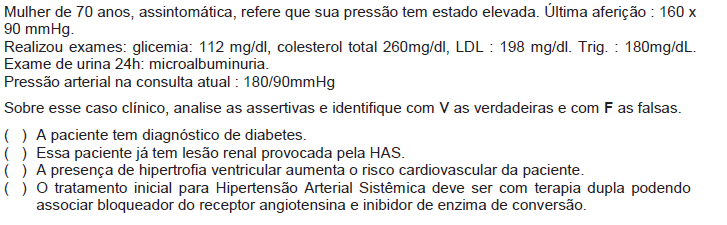

Homem de 64 anos é atendido na Policlínica com história de tontura e dor precordial constritiva há cerca de quatro horas. Refere um episódio de síncope nas últimas 24 horas. A figura 1 apresenta o eletrocardiograma (ECG) de admissão.

De acordo com o ECG apresentado na figura 1, é correto afirmar que